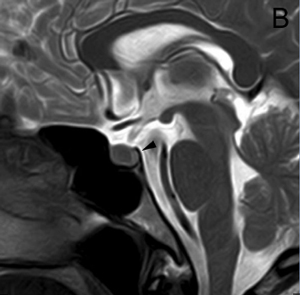

En los tumores grandes (macroadenomas) la TAC puede entregar información diagnóstica adecuada, pero no supera la definición que se logra con equipos de RM superconductores (Figuras 2 A y 2B).

Figura 2A y B. Cortes sagitales de RM y TAC. Adenoma pituitario con invasión del esfenoides y del clivus (puntas de flecha). Es posible demostrar las estructuras óseas en RM con similar precisión que la TAC.